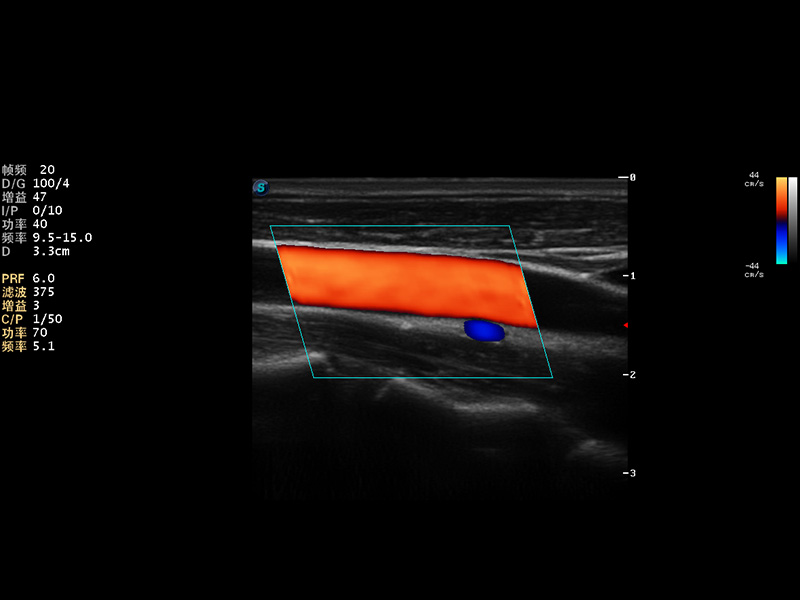

成像技术

AutoC智能血流追踪